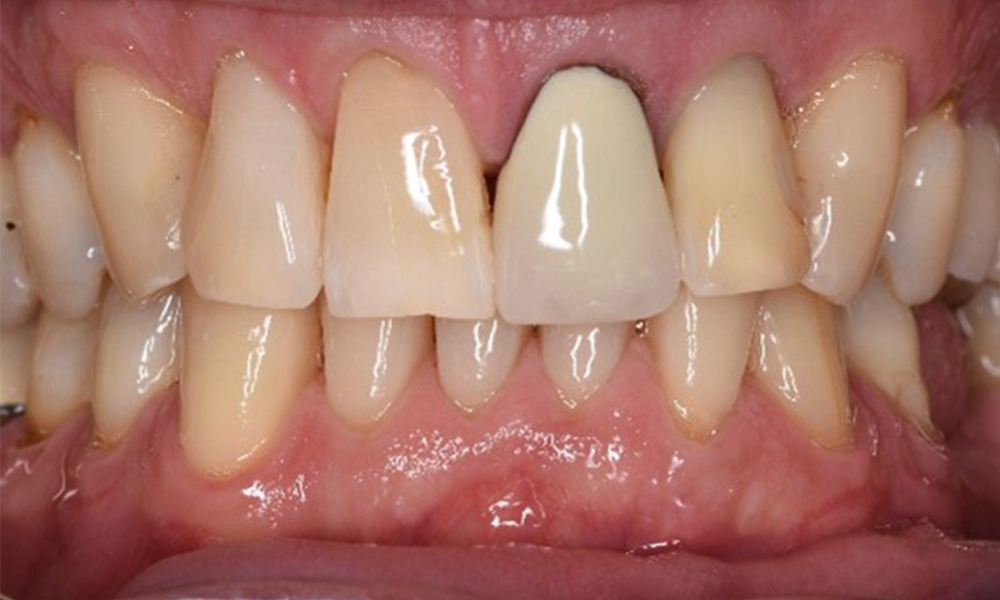

Der gesunde Patient mit parodontaler Vorerkrankung & Periimplantitis

Ein 52-jähriger Patient stellt sich zur Präventionssitzung vor. Der Patient hat keine Allgemeinerkrankungen und nimmt keine Medikamente ein. Er hat verschiedene zahnärztliche Versorgungen und zudem zwei aktive kariöse Läsionen. Außerdem verfügt der Patient über vier Implantate (2., 3. und 4. Quadrant). Es zeigt sich eine parodontale Vorerkrankung (Stadium IV, Grad B). Derzeit herrschen stabile parodontale Verhältnisse, lediglich am Implantat regio 36 zeigen sich Sondierungstiefen (ST) von 5 mm. Zudem lässt sich eine Gingivitis feststellen. mehr Infos